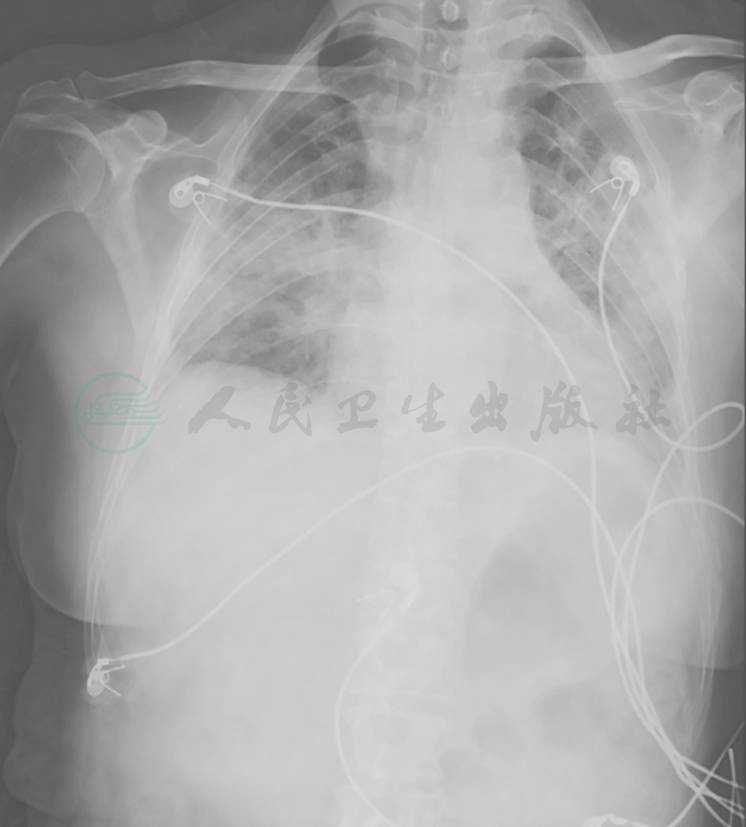

【影像学检查】

胸部X线检查可见双肺弥漫高密度影,双侧少量胸腔积液(图4),1个月后病灶进一步增多、加重(图5)。胸部CT显示病灶进一步融合增多,伴双侧胸腔积液和心包积液(图6)。

图4 胸部X线表现(2015-05-23)

胸部X线片可见双肺多发斑片影,双侧肋膈角显示不清,变钝

图5 胸部X线表现(2015-06-23)

胸部X线片可见双肺多发斑片影较前略加重,双肋膈角变钝